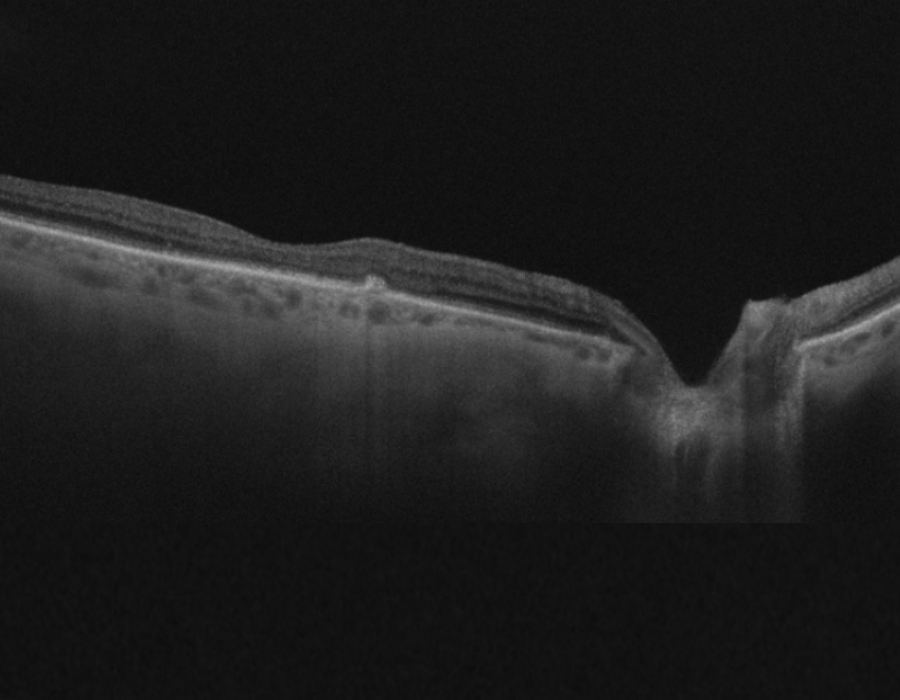

Depending on severity, Dry AMD is considered early, intermediate or late. In Dry AMD, vision loss is slower and likely due to age related thinning of the macula often accompanied by deposition of yellow protein clumps called Drusen in the macula.

AMD is one of the major causes of blindness in people >50 years of age. In this condition, the macula, which is the central part of the retina, gets affected and its cells start degenerating. AMD is progressive, i.e. the vision may keep worsening gradually, leading to loss of central vision which is responsible for the details in our vision. It requires regular monitoring to ensure timely treatment to try and preserve vision. Read more about AMD here